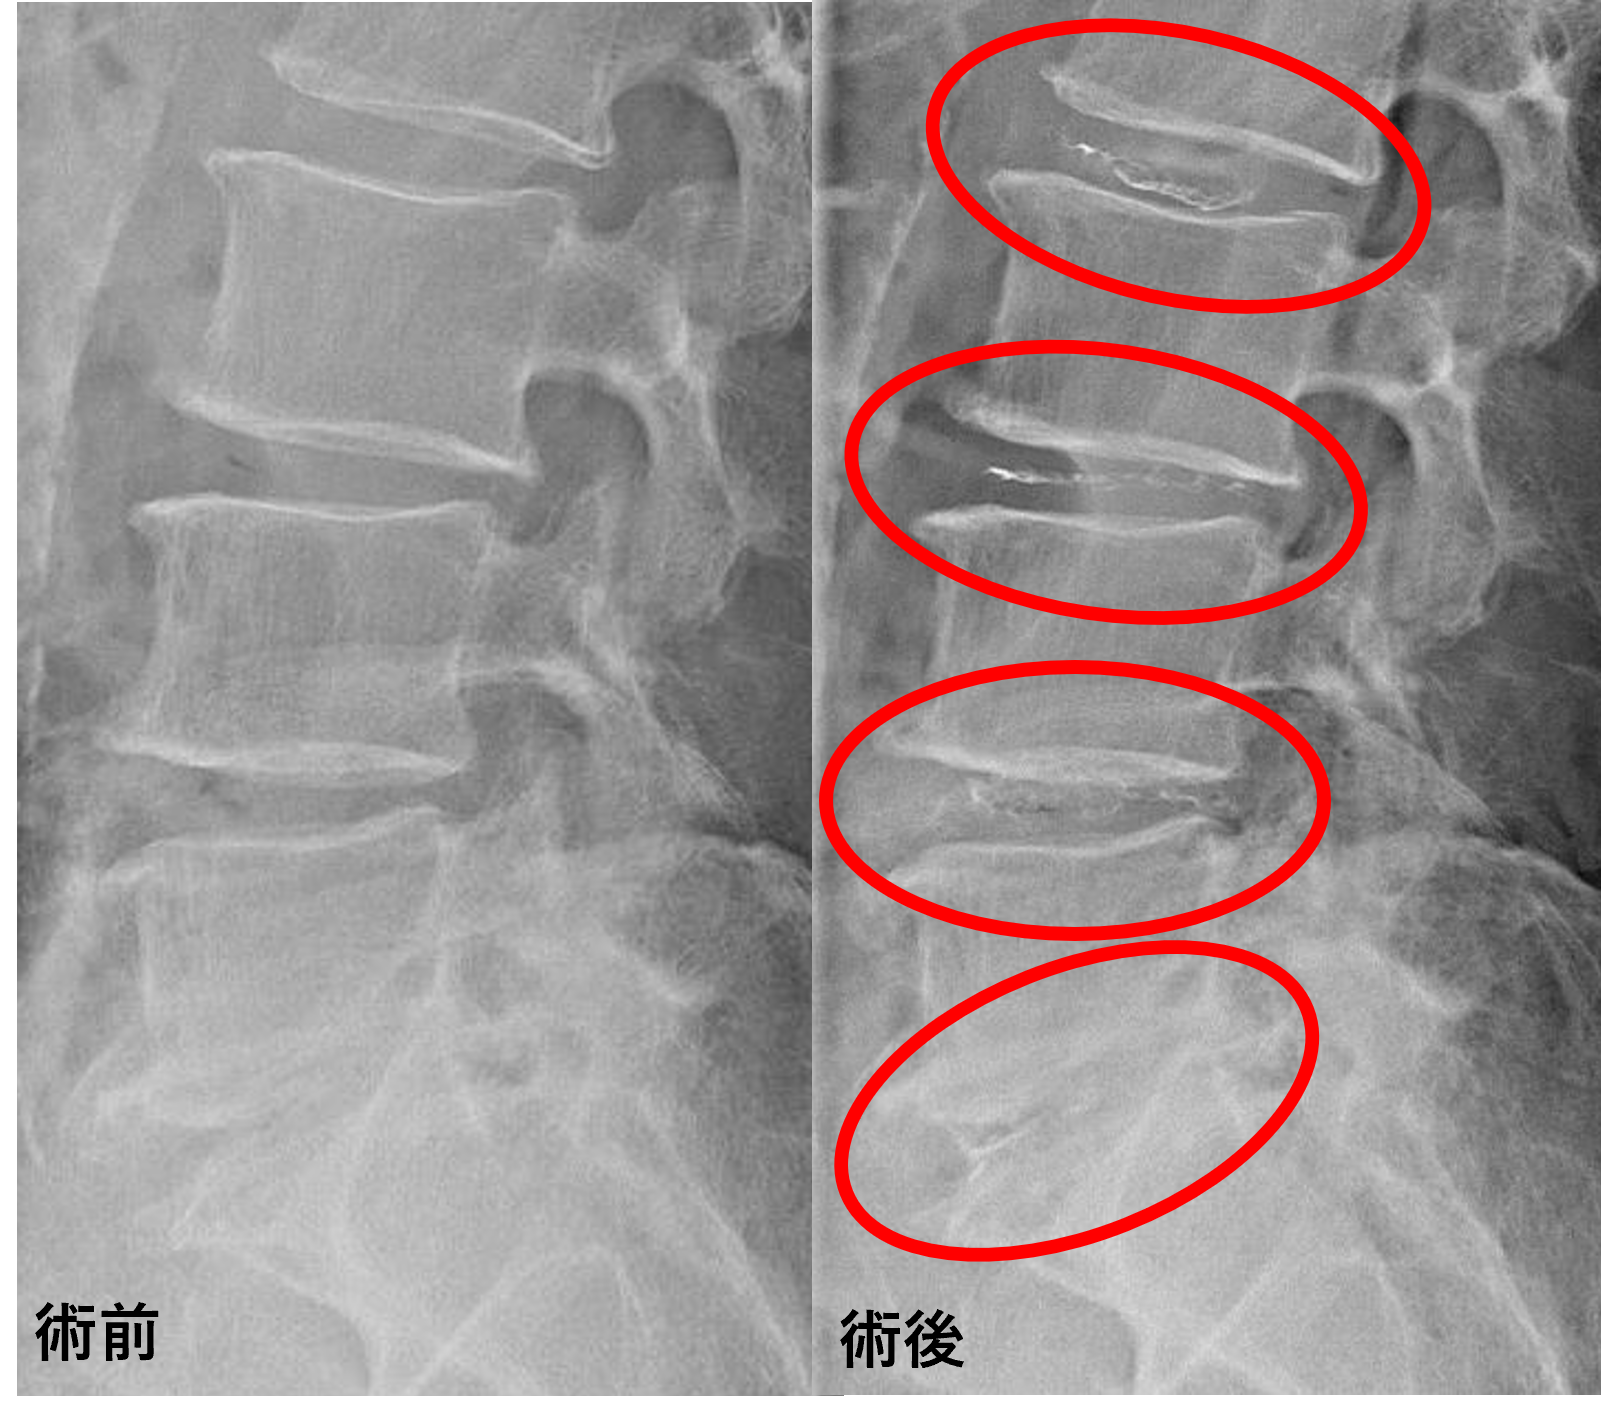

画像及び所見について

- L2/3、3/4 – 椎間板変性、膨隆

- L4/5 – 椎間板変性、膨隆、終板変性

- L5/s – 椎間板変性、膨隆、繊維輪断裂

以上のことが画像上認められました。

L2/3、3/4、4/5、5/sの椎間板所見による脊柱管の圧排が、症状の原因の可能性が高い。

患者様と相談の元、L2/3、3/4、4/5、5/sにセルゲル法を施行